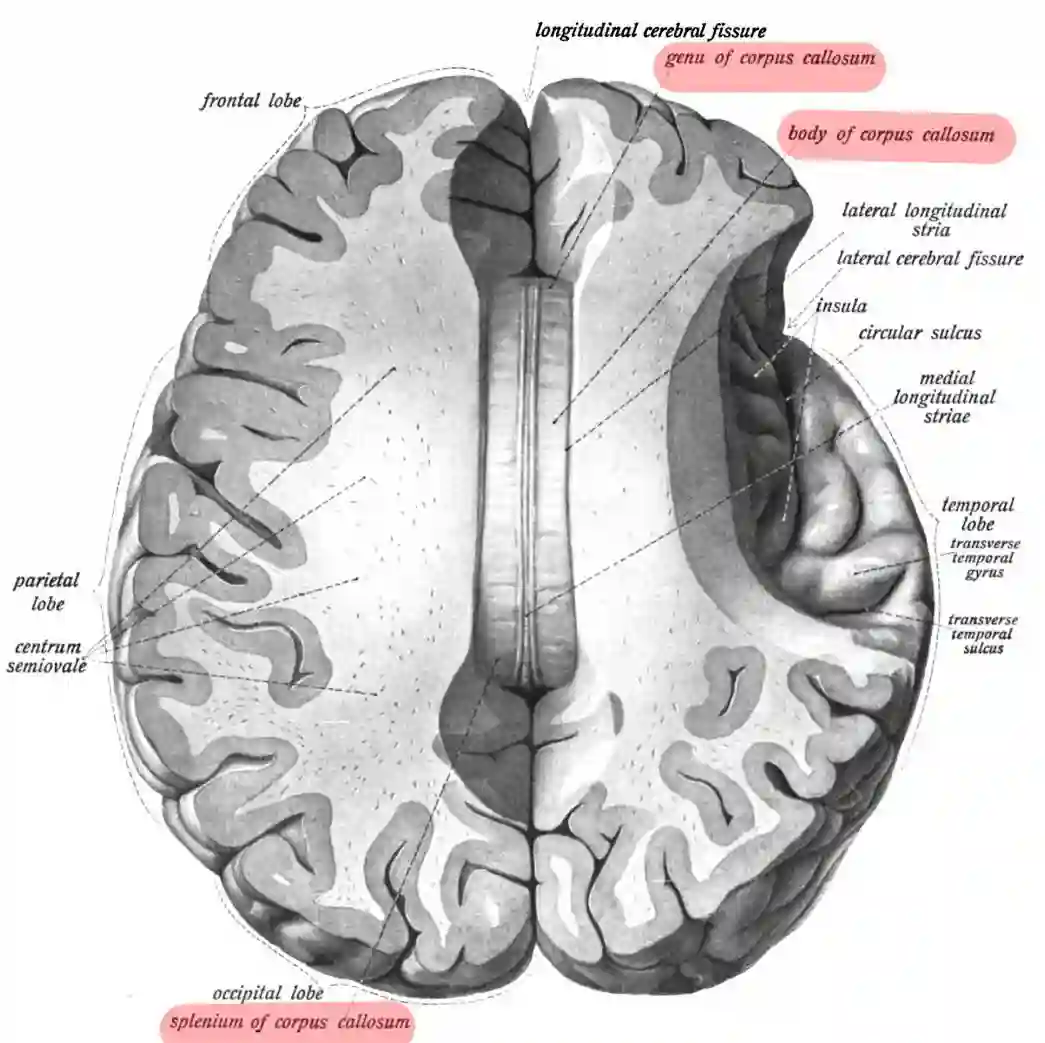

Abbildung

Schematische Abbildung des Corpus callosum in einer Ansicht von oben. Abbildung adaptiert von Sobotta.

Corpus Callosum